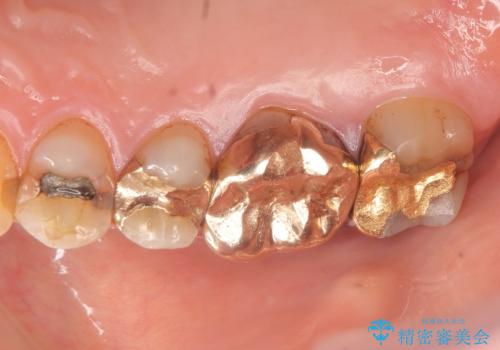

- 冷たいものがしみる右上の奥歯を治療して欲しいといらっしゃった方の症例です。

右上6,7の金歯を外したところ、虫歯が歯茎より深い位置まで進行していたため歯周外科を行いました。